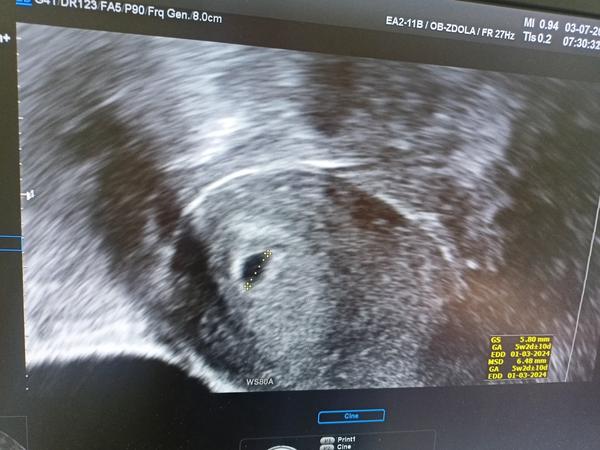

Ted ten problém:dnes jsem byla na ultrazvuku a nevidí tam nic. Vubec nic. Vzali mi krev, dle výsledků tam HCG je,ale jen mírné hodnoty. Doktorka mi řekla že bud za A,je ještě brzy,za B,to není prosperují těhotenství,C, se jedná jen o chemické těhotenství,a nebo za D,o mimoděložní (vyšetřila mě předtím než mi vzali krev.

Tak mi to nedalo a zašla jsem si jako samoplatce na test HCG. Z 120,9(v pondělí) dnes vzrostl na 641,5 (čtvrtek) . Volala jsem na gyndu a rikali mi, že jsem prostě asi otěhotněla později, a že v pondělí budu odcházet s úsměvem. Tak mi držte palce aby se paní Bobulka ukazala i na ultrazvuku